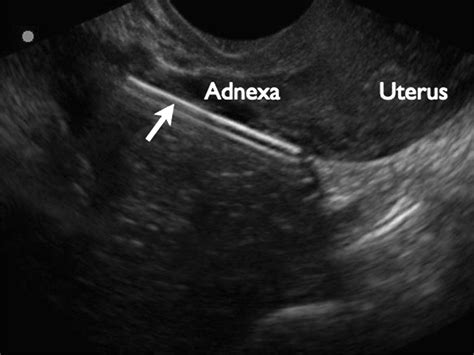

When a physician suspects a perforation, they will typically initiate a diagnostic process to determine the extent of the damage. Imaging technologies play a vital role here. A transvaginal ultrasound is often the first line of defense, as it can help locate an misplaced IUD or detect free fluid in the pelvic cavity that might indicate bleeding. In more complex scenarios, a CT scan or MRI may be required to visualize the abdominal cavity more clearly and rule out injury to the bowel, bladder, or major arteries.